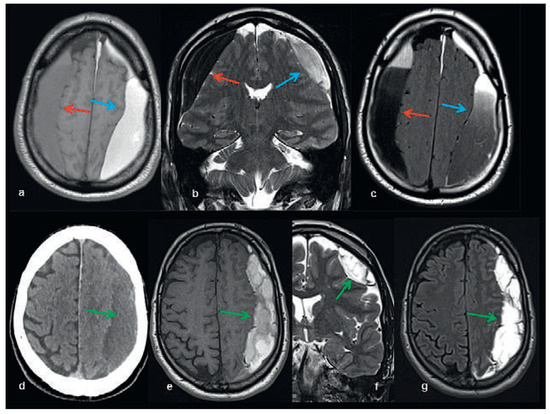

Head and brain trauma: general aspects and neuroimaging

by Johanna Maria Lieb, Christoph Stippich and Meritxell Garcia

In this article the general clinical aspects, imaging indications and different injury mechanisms of traumatic brain injury (TBI) are reviewed. In addition, the different imaging modalities and strategies are presented, including more specific imaging features of the various injuries. Computed tomography (CT) is [...] Read more.

In this article the general clinical aspects, imaging indications and different injury mechanisms of traumatic brain injury (TBI) are reviewed. In addition, the different imaging modalities and strategies are presented, including more specific imaging features of the various injuries. Computed tomography (CT) is the imaging modality of choice in the acute phase owing to its wide availability and short scanning time, as well as to its high sensitivity for the detection of fractures and acute bleeding. Although magnetic resonance imaging (MRI) is superior to CT in many other aspects, it plays no role in the acute phase. MRI, however, has been proven to be useful and complementary to CT in the subacute and chronic stages as well as in the case of inconclusive results on initial CT. Especially the use of standard sequences like fluid attenuated inversion recovery (FLAIR), diffusion and susceptibility weighted imaging (DWI and SWI) have been shown to increase the diagnostic potency in diffuse axonal injury, in mild brain trauma and also in more chronic stages of TBI. The use of more advanced MRI techniques such as diffusion tensor imaging (DTI), magnetic resonance spectroscopy (MRS), functional MRI (fMRI) and magnetic transfer imaging (MTI) can further complete the diagnostic evaluation and give insights into different pathophysiological processes in TBI. Full article